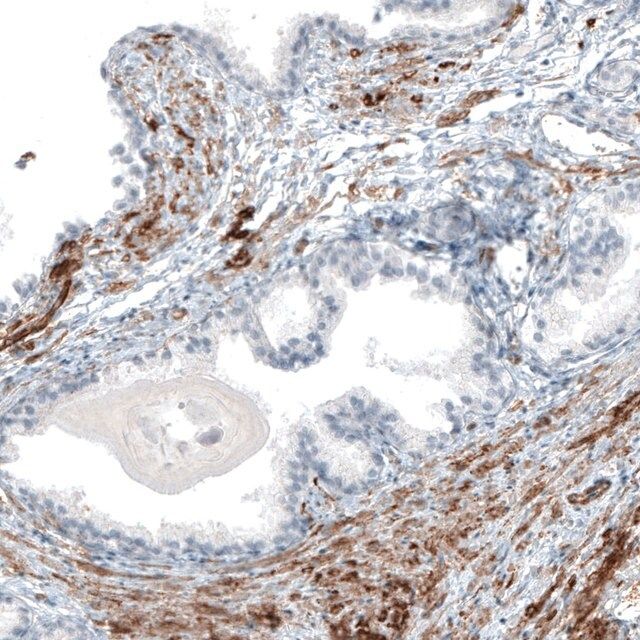

All Prestige Antibodies Powered by Atlas Antibodies are developed and validated by the Human Protein Atlas (HPA) project (www.proteinatlas.org)and as a result, are supported by the most extensive characterization in the industry. The Human Protein Atlas project can be subdivided into three efforts: Human Tissue Atlas, Cancer Atlas, and Human Cell Atlas. The antibodies that have been generated in support of the Tissue and Cancer Atlas projects have been tested by immunohistochemistry against hundreds of normal and disease tissues and through the recent efforts of the Human Cell Atlas project, many have been characterized by immunofluorescence to map the human proteome not only at the tissue level but now at the subcellular level. These images and the collection of this vast data set can be viewed on the Human Protein Atlas (HPA) site by clicking on the Image Gallery link. To view these protocols and other useful information about Prestige Antibodies and the HPA, visit sigma.com/prestige.

- IHC tissue array of 44 normal human tissues and 20 of the most common cancer type tissues.